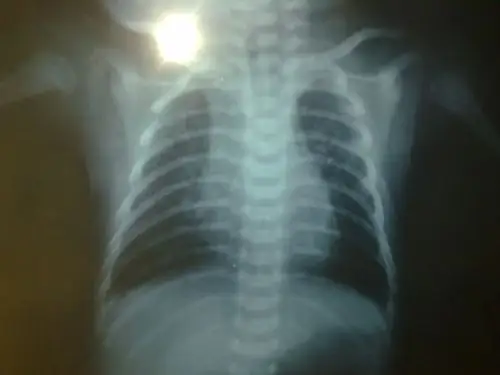

问题:20天宝宝在医院影像科诊断上写的是 支气管肺炎 该怎么办